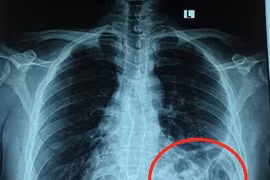

Ho, khó thở tưởng hậu Covid-19, nam thanh niên 25 tuổi cố chịu đựng điều trị tại nhà. Khi ho và tức ngực không chịu được bệnh nhân mới đi khám mới hay thoát vị hoành trái do vỡ cơ hoành.